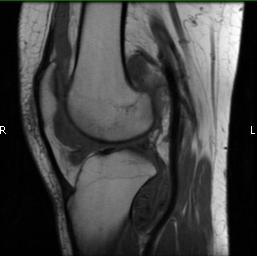

MRI (Fig. 1-10)

- Periarticular or synovial nodular mass with varying degrees of bone erosion.

- Nodular lesion with areas of hemosiderin (low signal on all sequences) and hemorrhage.

- On fat suppress images the tumor is high signal and hemosiderine cannot be seen.

- Joint effusions and bony erosions are well demonstrated. As with CT, contrast enhancement is typical.

Fig. 1-10: Magnetic Resonance of a PVNS of the knee shows a synovial mass with minimal bone erosion of the medial articular plate. On T1W and T2W images shows a tumor with low intensity areas (hemosiderin) and hemorrhage. Joint effusion is well demonstrated. Post contrast images demonstrate an irregular pattern of enhancement.